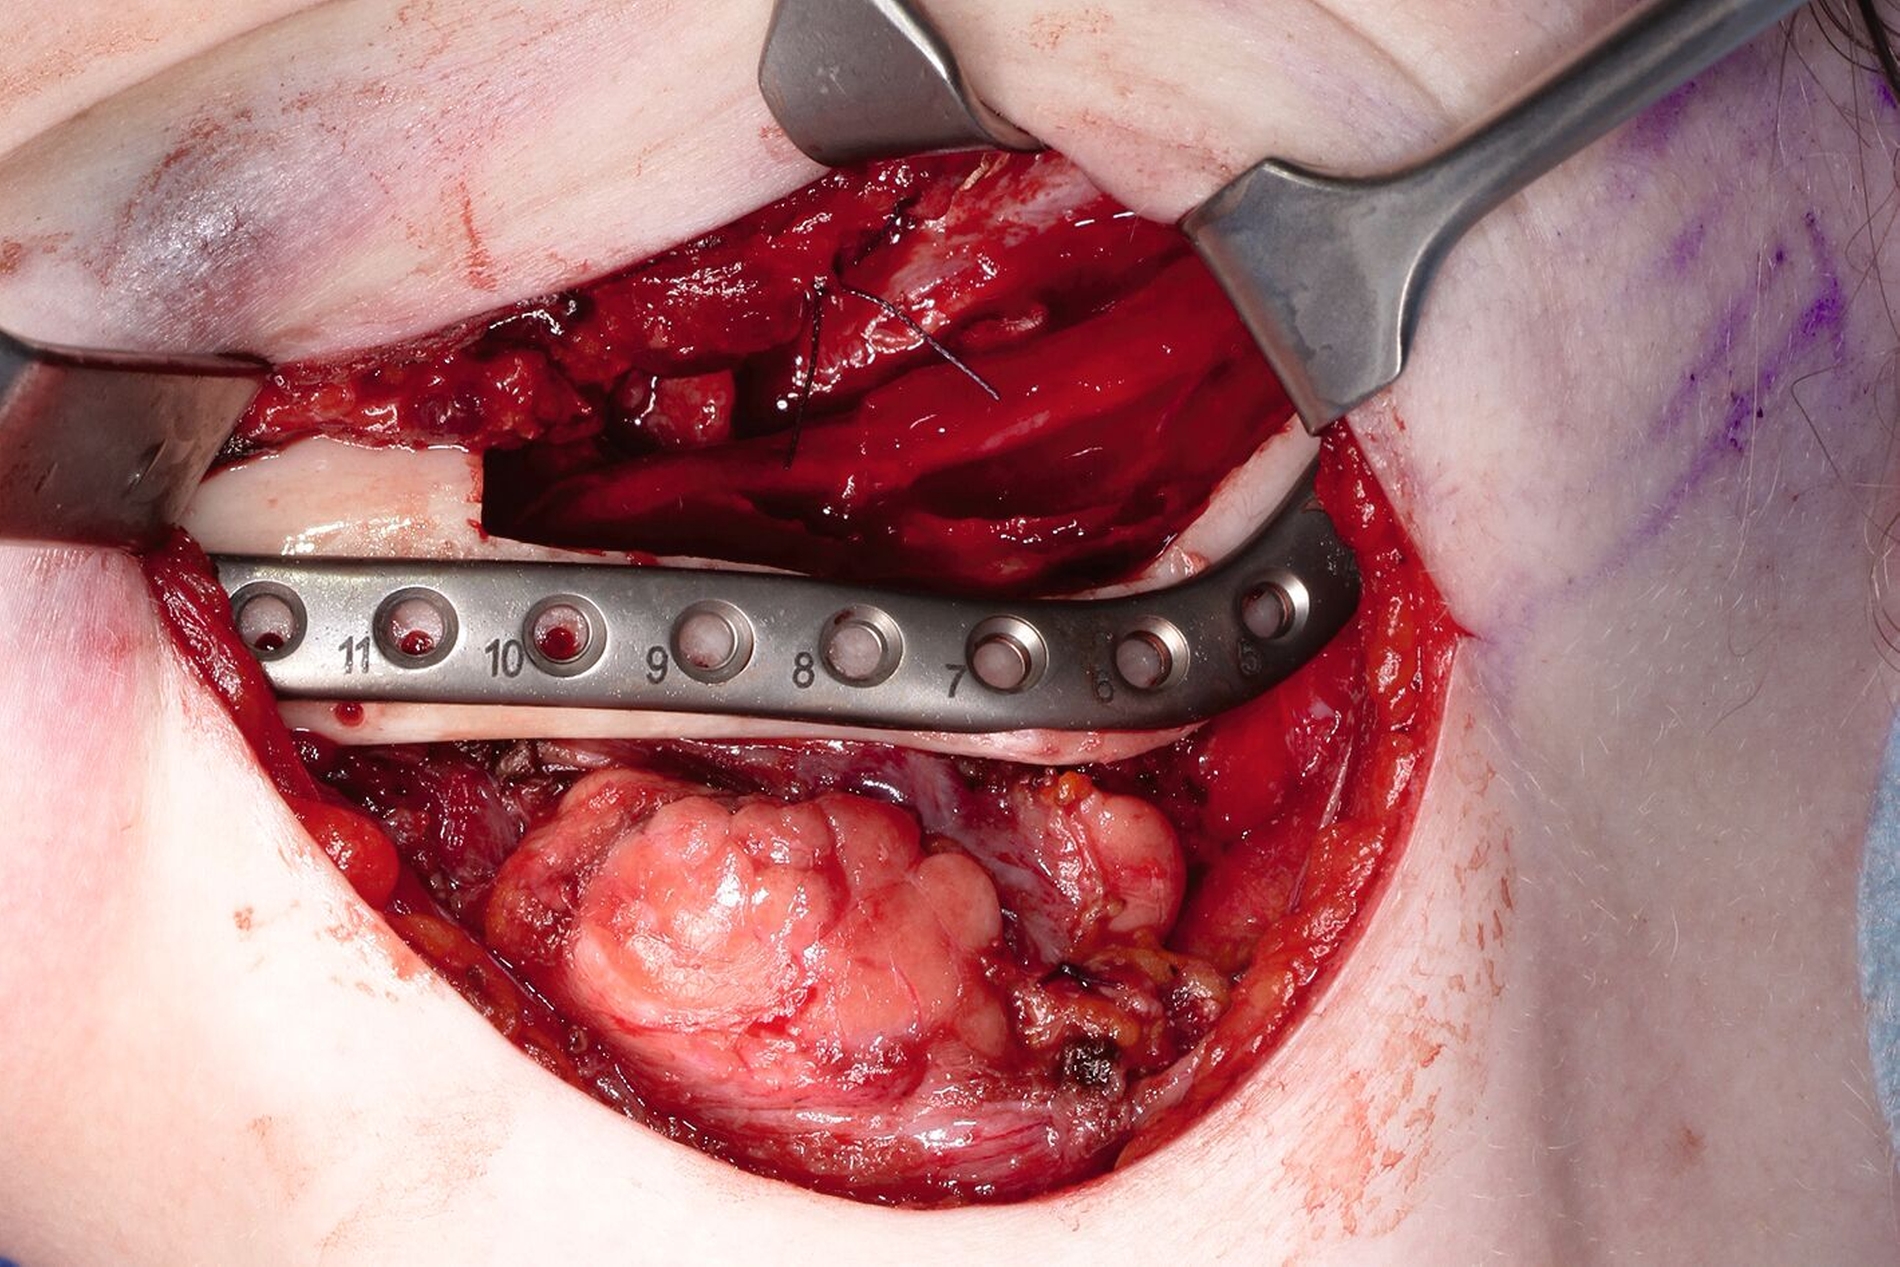

Der Eingriff erfolgte über einen submandibulären Zugang in Intubationsnarkose. Intraoperativ zeigte sich eine starke Auftreibung der Kortikalis des Ramus ascendens. Der aufsteigende Unterkieferast wurde nahezu vollständig subperiostal dargestellt, das anhängende Weichgewebe mit dem Raspatorium gelöst. Die Resektionsschablone wurde eingebracht und die geplante Schnittführung mit dem Piezo markiert.

Anschließend wurde die Resektionsschablone wieder entfernt und der N. alveolaris inferior ebenfalls mit dem Piezo aus seinem Bett herausgelöst und nach lateral neurolysiert. Erst danach erfolgte die vollständige Resektion des Tumors entsprechend der Resektionsmarkierung. Der Tumor konnte en bloc entfernt werden (Abbildung 5).

Der N. alveolaris inf. wurde zurück in sein ursprüngliches Bett verlagert und mit Fibrinkleber bedeckt. Nun erst wurde die Rekonstruktionsosteosyntheseplatte eingebracht und entsprechend der Planung verschraubt. Zur Augmentation des resektionsbedingten Knochenverlusts erfolgte die Transplantation zweier kortikospongiöser Beckenkammspäne von der rechten Spina iliaca anterior in den Defekt. Die Knochenblöcke wurden mit einer konventionellen Osteosyntheseplatte fixiert (Abbildung 6).

Der Zahn 37 befand sich in unmittelbarer Nähe zum Resektionsrand. Ein Versuch, den Zahn zu erhalten, hätte eine vollständige Exposition der distalen Wurzel bedeutet, so dass stattdessen die Extraktion erfolgte. Der Bereich der Extraktionsalveole stellte die einzige Verbindung der Wundfläche zur Mundhöhle dar, die lokal plastisch verschlossen werden konnte. Der nicht erhaltungswürdige Zahn 28 wurde anschließend auf Patientenwunsch ebenfalls entfernt.